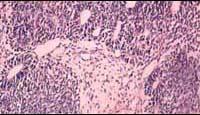

问题 关于肾母细胞瘤的描述中不正确的是()

选项 A.多数在5岁以前发病 B.2/3在3岁以内发病 C.男女发病数相近 D.左右侧发病相近 E.成人不发病

答案 E